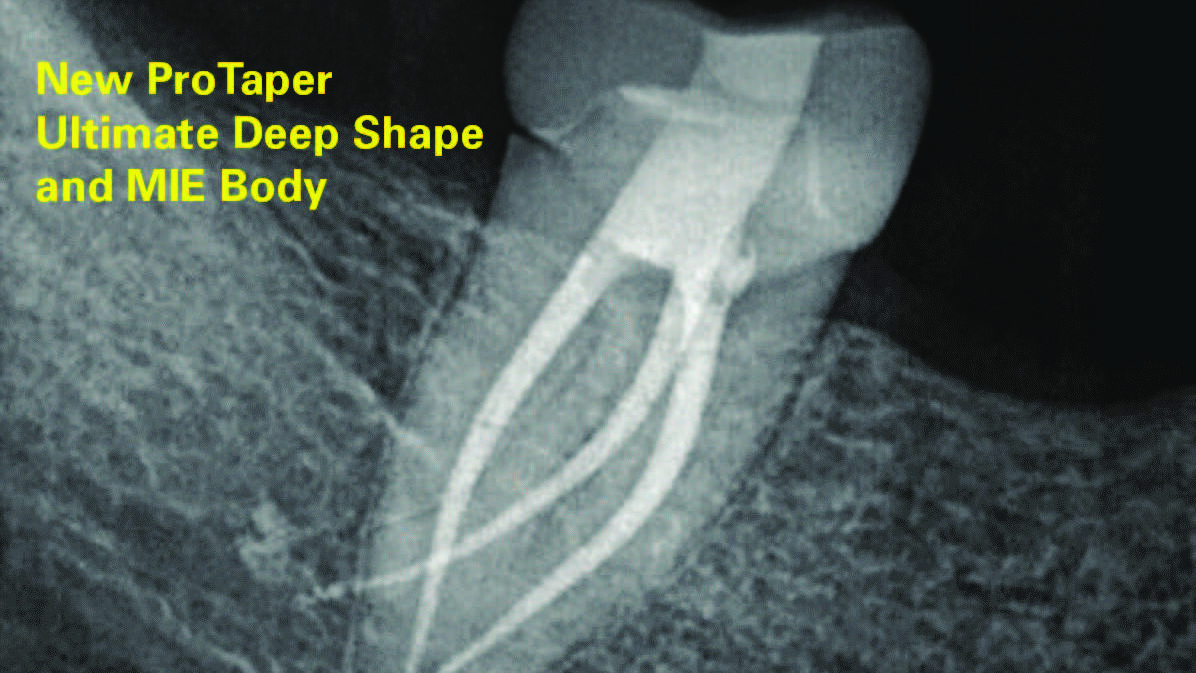

Why Endodontic Therapy is the Treatment of Choice in Patients on Anti-Resorptive Drug Therapy

The most common odontogenic infection is that of the periapical tissues most frequently caused by dental caries, a deep restoration, or failed root canal treatment.1 Apical periodontitis (AP) has been found to have a prevalence of 50% in patients under the age of 50, and the prevalence and risk of AP has been found to be … Read more